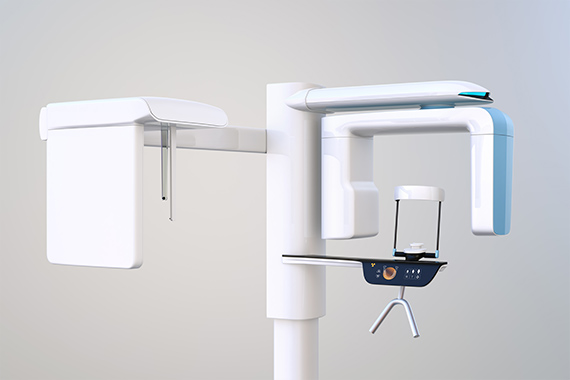

歯科用CTによる

精度の高い検査・診断

根管の数や形状は個人差が大きく、事前にできる限り詳細に状態を確かめることが大切です。当院では、歯科用CTの鮮明な3D画像を用いて、患者さんごとに異なる根管の様子を正確に把握します。その上で、そのかたの根管の状態に適した治療計画を立案することで、より確実性の高い治療の提供を目指しています。